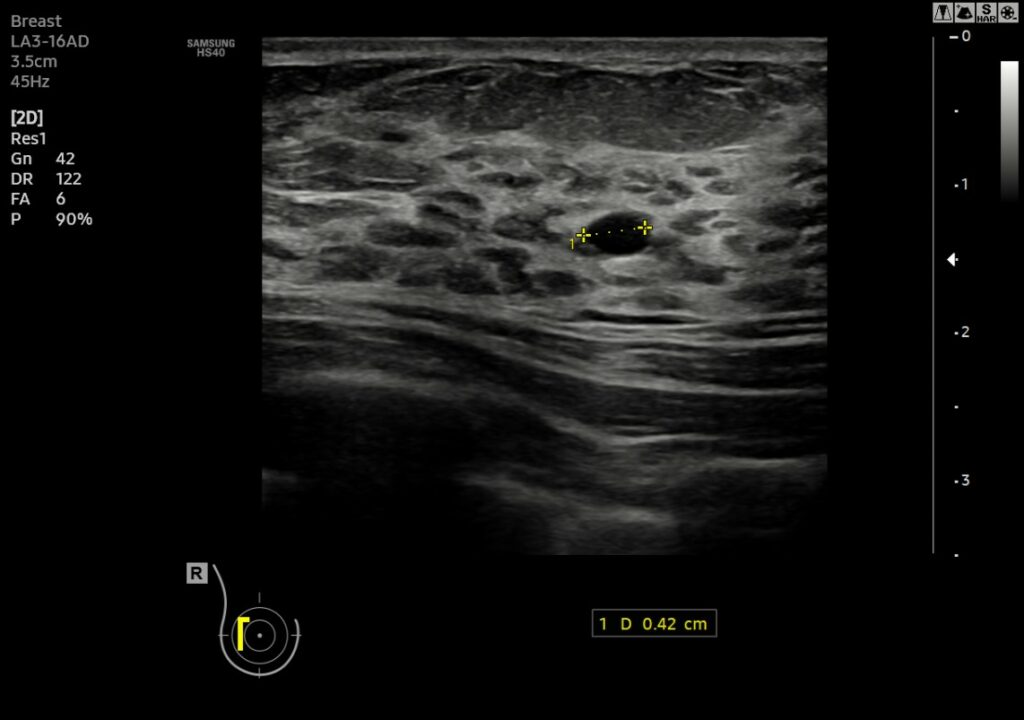

USG piersi to nieinwazyjne, bezpieczne i bezbolesne badanie obrazowe, które pozwala ocenić strukturę tkanek gruczołu piersiowego i wykryć zmiany takie jak torbiele, guzki czy inne nieprawidłowości. W naszej placówce w Gliwicach wykonujemy badania przesiewowe piersi zarówno diagnostyczne, jak i profilaktyczne.

U kobiet po 40. roku życia USG piersi nie zastępuje mammografii – oba badania mają różne właściwości diagnostyczne i powinny być stosowane łącznie. Mammografia lepiej wykrywa zwapnienia i mikrozwapnienia typowe dla wczesnych form raka, natomiast USG pozwala dokładniej zobrazować zmiany w gęstym gruczole piersiowym. Lekarz podejmuje decyzję o zakresie badań indywidualnie.

Wynik badania USG klasyfikowany jest zgodnie z systemem BIRADS (Breast Imaging Reporting and Data System):

BIRADS 0 – wynik niepełny, konieczne są dalsze badania

BIRADS 1 – obraz prawidłowy, brak zmian

BIRADS 2 – zmiany łagodne (np. torbiele), bez ryzyka

BIRADS 3 – zmiana prawdopodobnie łagodna, zalecana kontrola za 6 miesięcy

BIRADS 4 – zmiana podejrzana, wymaga biopsji

• 4A – niskie ryzyko

• 4B – pośrednie ryzyko

• 4C – wysokie ryzyko -

BIRADS 5 – zmiana wysoce podejrzana o złośliwość, konieczna szybka diagnostyka

BIRADS 6 – nowotwór złośliwy już potwierdzony histopatologicznie

Każda pacjentka otrzymuje szczegółowy opis badania wraz z kwalifikacją BIRADS, co pozwala na dalsze, odpowiednie postępowanie diagnostyczne lub terapeutyczne.